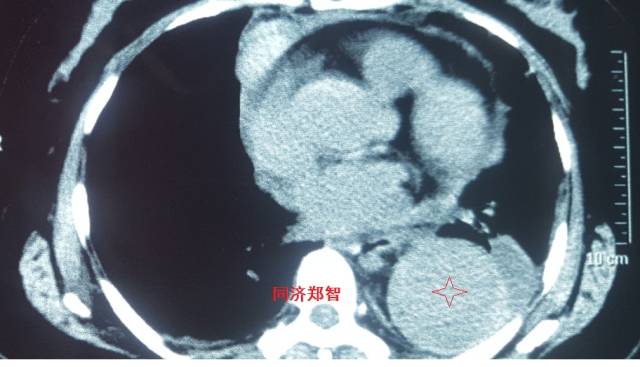

病例十

腹主动脉平扫CT提示正常外周一圈的钙化影中有内移的钙化影(红色箭头所示),CTA 证实为腹主动脉夹层

图19-20